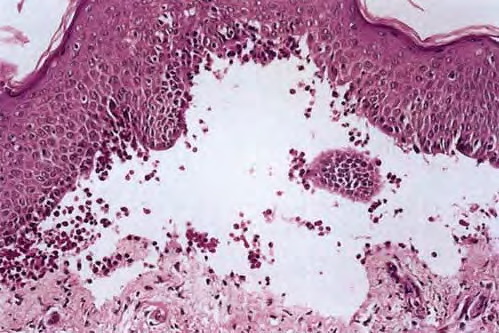

Hailey Hailey disease= ุงูููุงุน ุงูุนุงุฆูู ุงูุณููู ูููู ูููู HaileyHailey Disease Familial benign pemphigus is inherited as an autosomal dominant trait, with a family history obtainable in about two thirds of patients. Genetic studies have localized the key mutations to the ATP2C1 gene on chromosome 3q , specifically 3q21-q24, the area responsible for ATP-dependent calcium transport […]